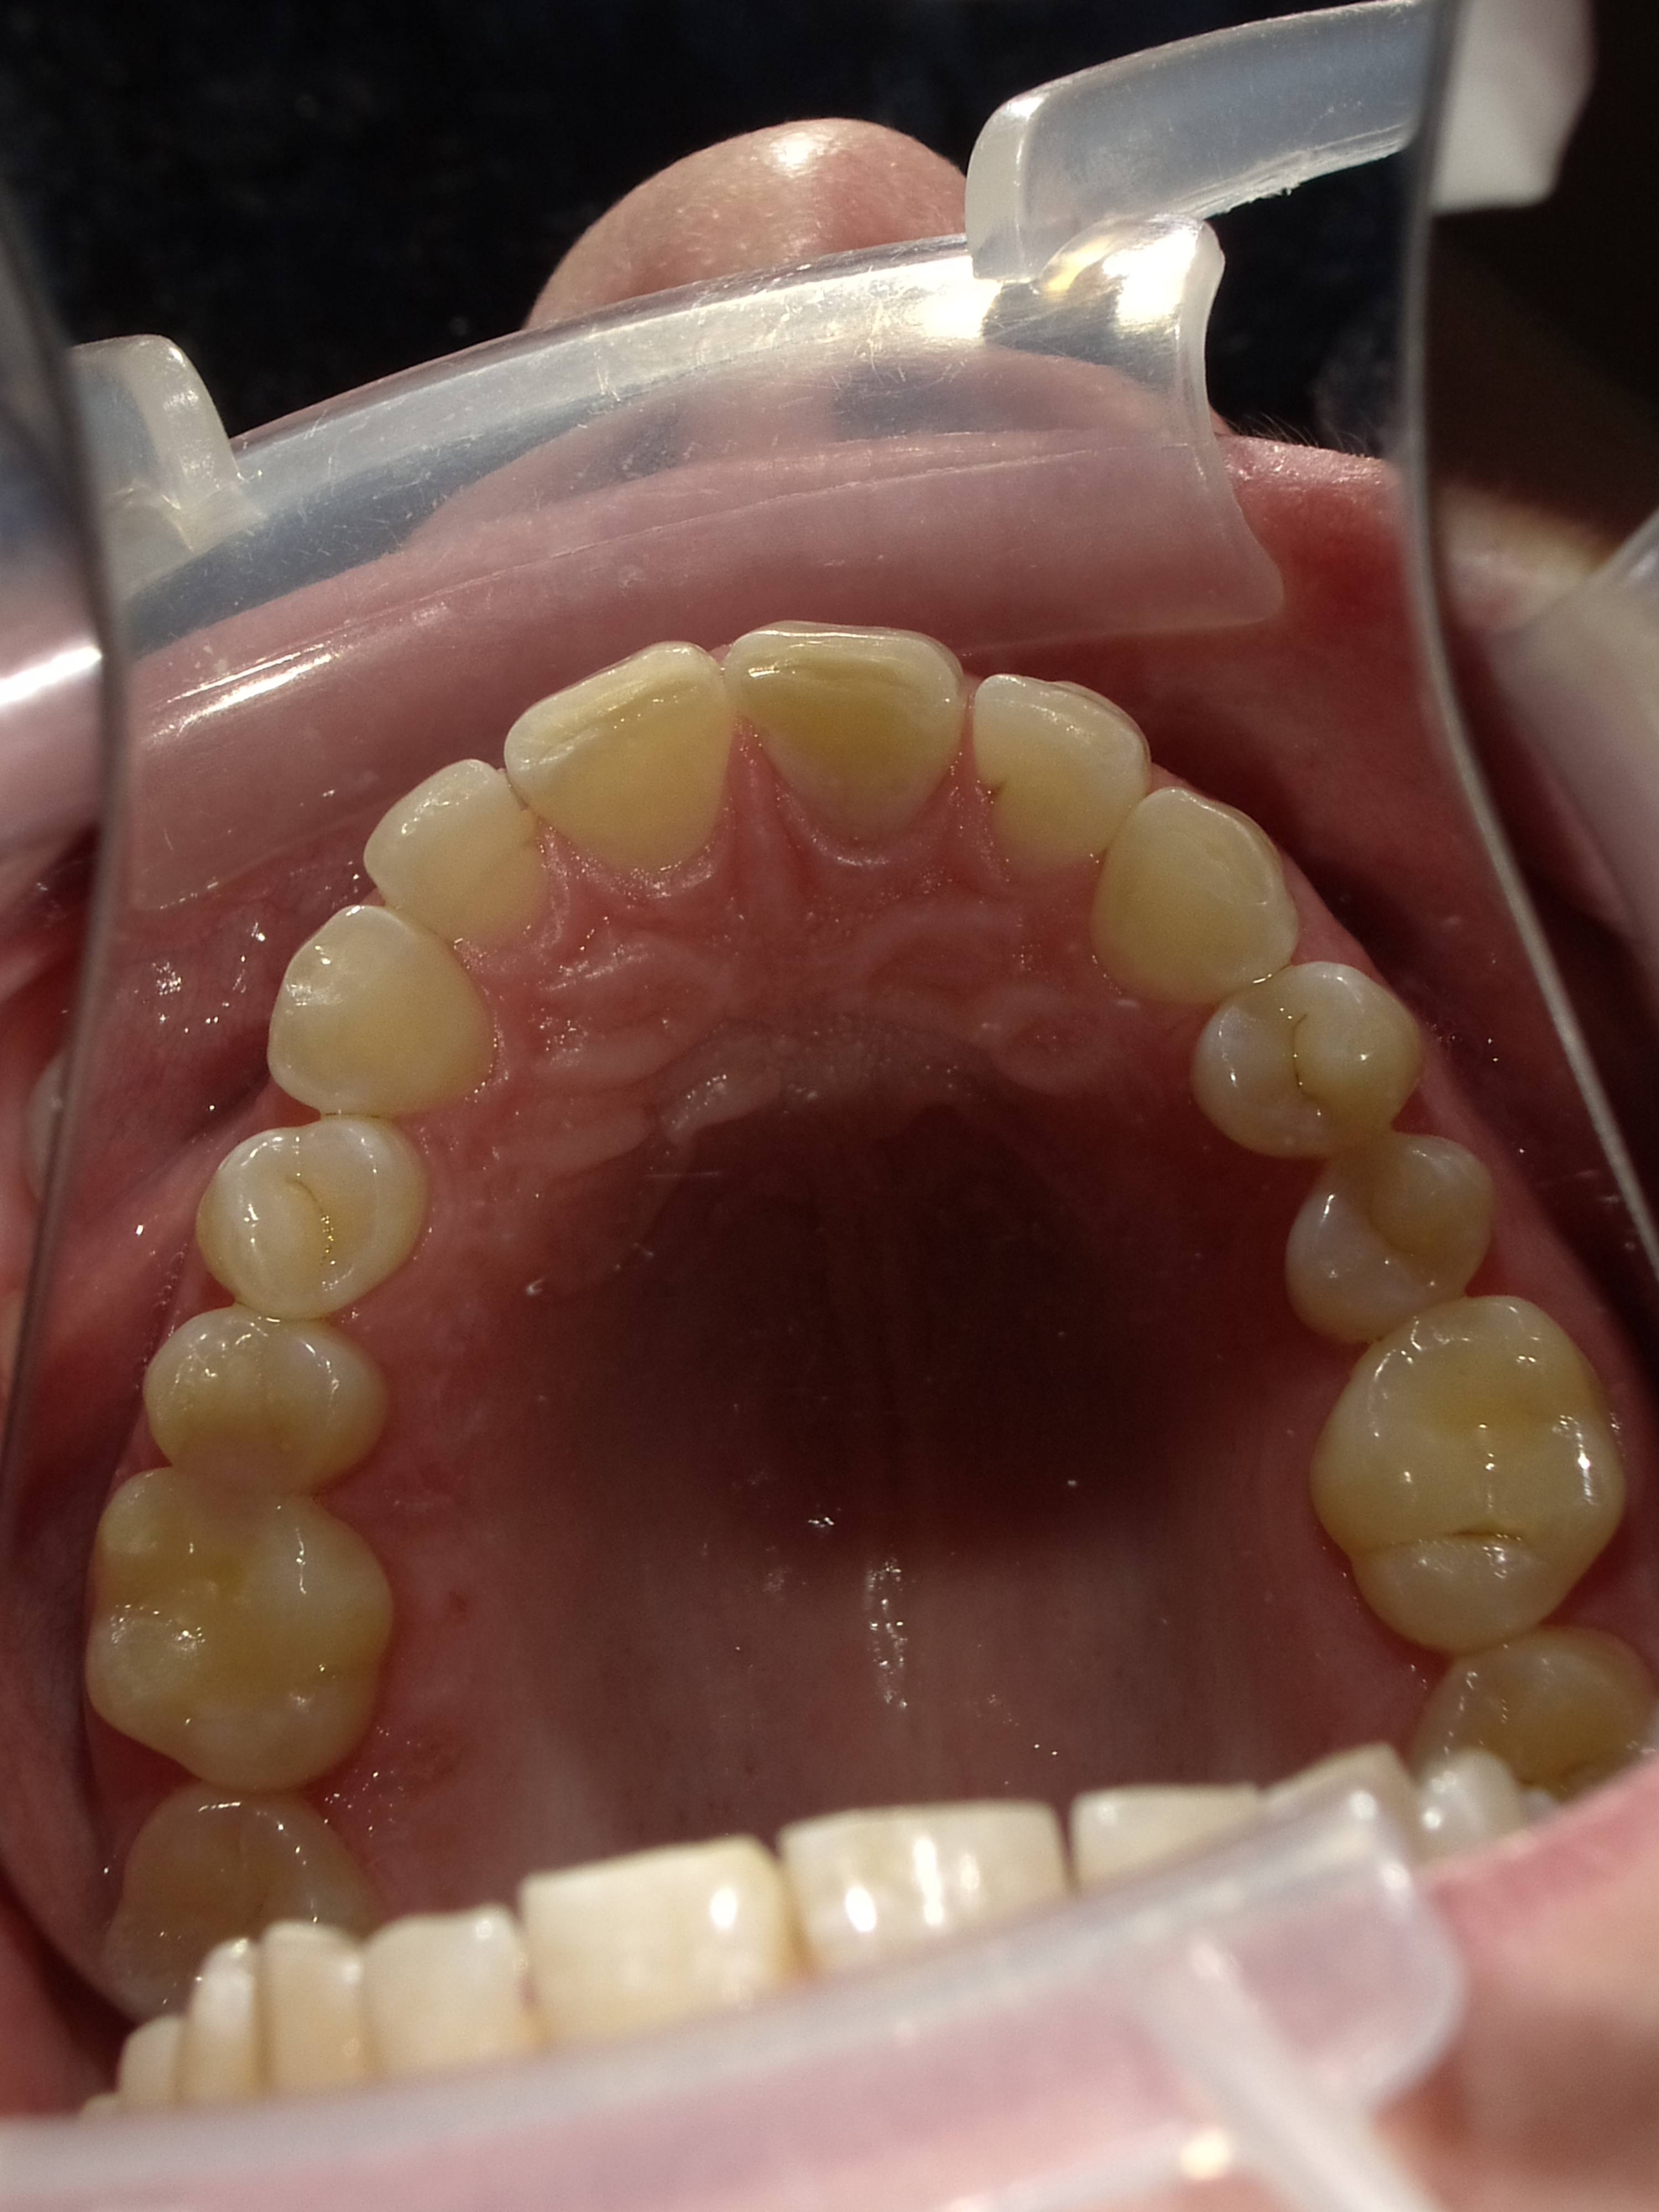

Patient Photographs

At a minimum, 4 photos are required.

1. Front view smile not retracted

2. Front view retracted

3. Maxilary retracted (with mirror is best.

4. Mandibular retracted.

Good lighting is key. A cell phone can be used with flash.